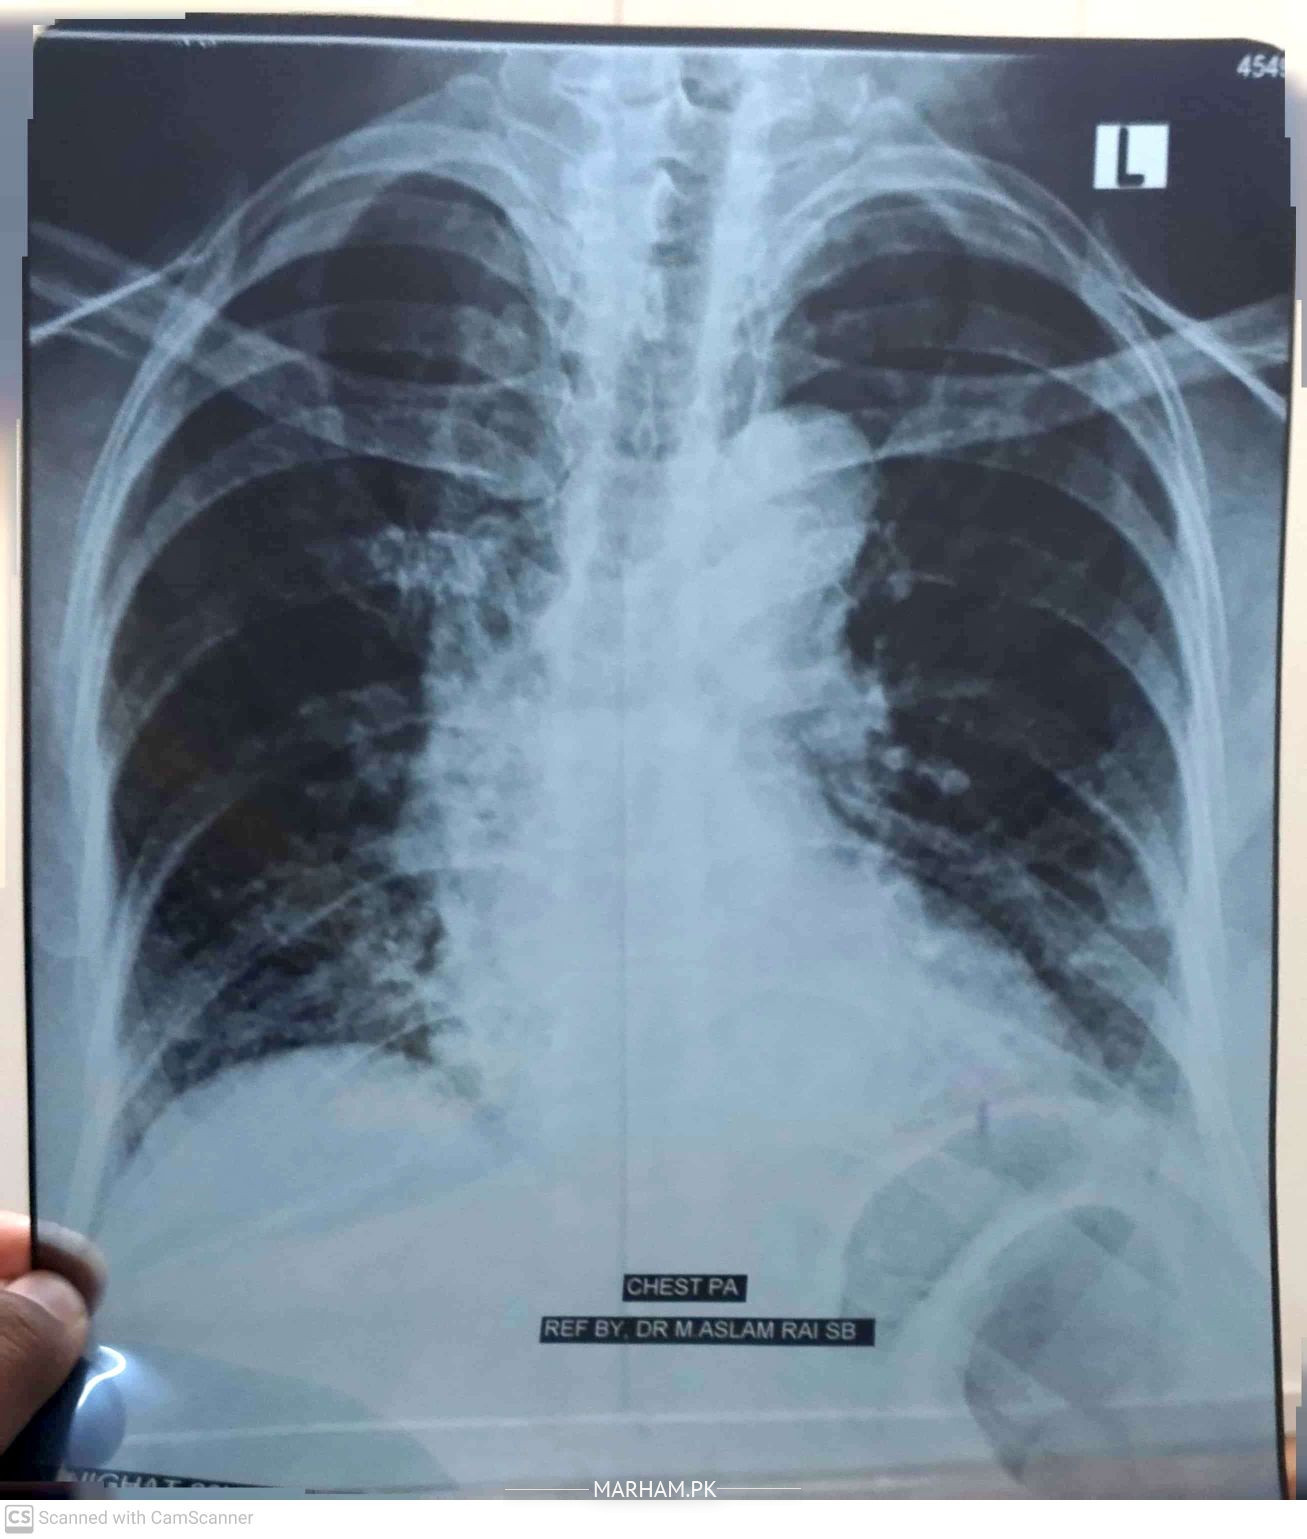

Talk to Pulmonologist / Lung on Chest X-ray

Slam, mother ki age 60 years, chest x-ray krwaia ha, plz is k regarding guide kr dein k shi ha ya nhi?

Interstitial Lung disease Ka masla ho sakta hy. Physical Check up karwayen aur HRCT chest karwayen .

any complaints ur mother is having?

proper history and evaluation needed